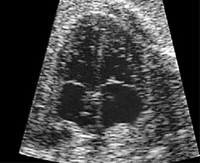

Врач, оценивая сердцебиение и ЧСС плода, одновременно занимается исследованием анатомии (строения) формирующейся сердечно сосудистой системы будущего ребеночка. Наиболее информативно в этом плане УЗИ, проводимое на 18-28-й неделях. К этому сроку беременности структурные особенности хорошо различимы.

Оптимальные данные получают при методике четырехкамерного среза, когда достаточно четко визуализированы оба желудочка, предсердия (правое и левое), можно рассмотреть перегородки — межжелудочковую и межпредсердную, створки митрального и трикуспидального клапана, клапан овального отверстия.

Во втором триместре оптимальное изображение четырехкамерного среза удается при абсолютном большинстве УЗИ (у 90%). Если оно свидетельствует о норме, то дальнейшие обследования проводятся в стандартном, плановом режиме.